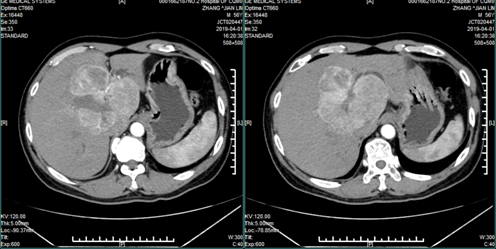

2019年4月10日,在重庆市肝胆外科首席专家工作室领衔专家龚建平主任指导下,我院肝胆外科刘作金教授团队完成了一例罕见的难度极大的累及肝左右交界区及尾状叶的巨大混合肿瘤切除术。患者章某某,男性,56岁,来自贵州省遵义市。他4年前于新桥医院行CT检查,发现5厘米肝占位病变,肝穿刺活检提示肝神经内分泌瘤可能,行射频消融治疗后出院;3月前于西南医院再次复查时提示肝占位增大至10厘米,而再次行射频消融治疗。但因肿瘤巨大,部位特殊(推挤右肝静脉,侵润压迫中肝、左肝静脉),射频效果欠佳。术后CT复查提示肿瘤活性仍存且继续增大(12厘米)。随即患者及家属辗转于重庆市各三甲医院,均被告知因肿瘤巨大且部位特殊已无治疗机会。万幸的是,绝望回到遵义的章某有一邻居曾在我院治疗肝病,附二院精湛的医技,高尚的医德给他留下了深刻的印象。如同抓住最后一根救命稻草的章某抱着最后一线希望来到我院肝胆外科求治。

龚建平主任主持了全科讨论,认为肿瘤体积虽然巨大、且紧贴右肝静脉及下腔静脉,但边界较为清楚仍有切除机会,不过手术难度极大。在完成必要术前准备后,在龚建平主任指导下,刘作金教授团队历时7小时10分钟,顺利完成手术。现患者康复良好即将出院,术后病理提示:肝神经内分泌肿瘤及肝细胞性肝癌。文献检索提示,同时生长这两种类型肿瘤的病例极其罕见,但因肿瘤完整切除,术后预后较好。